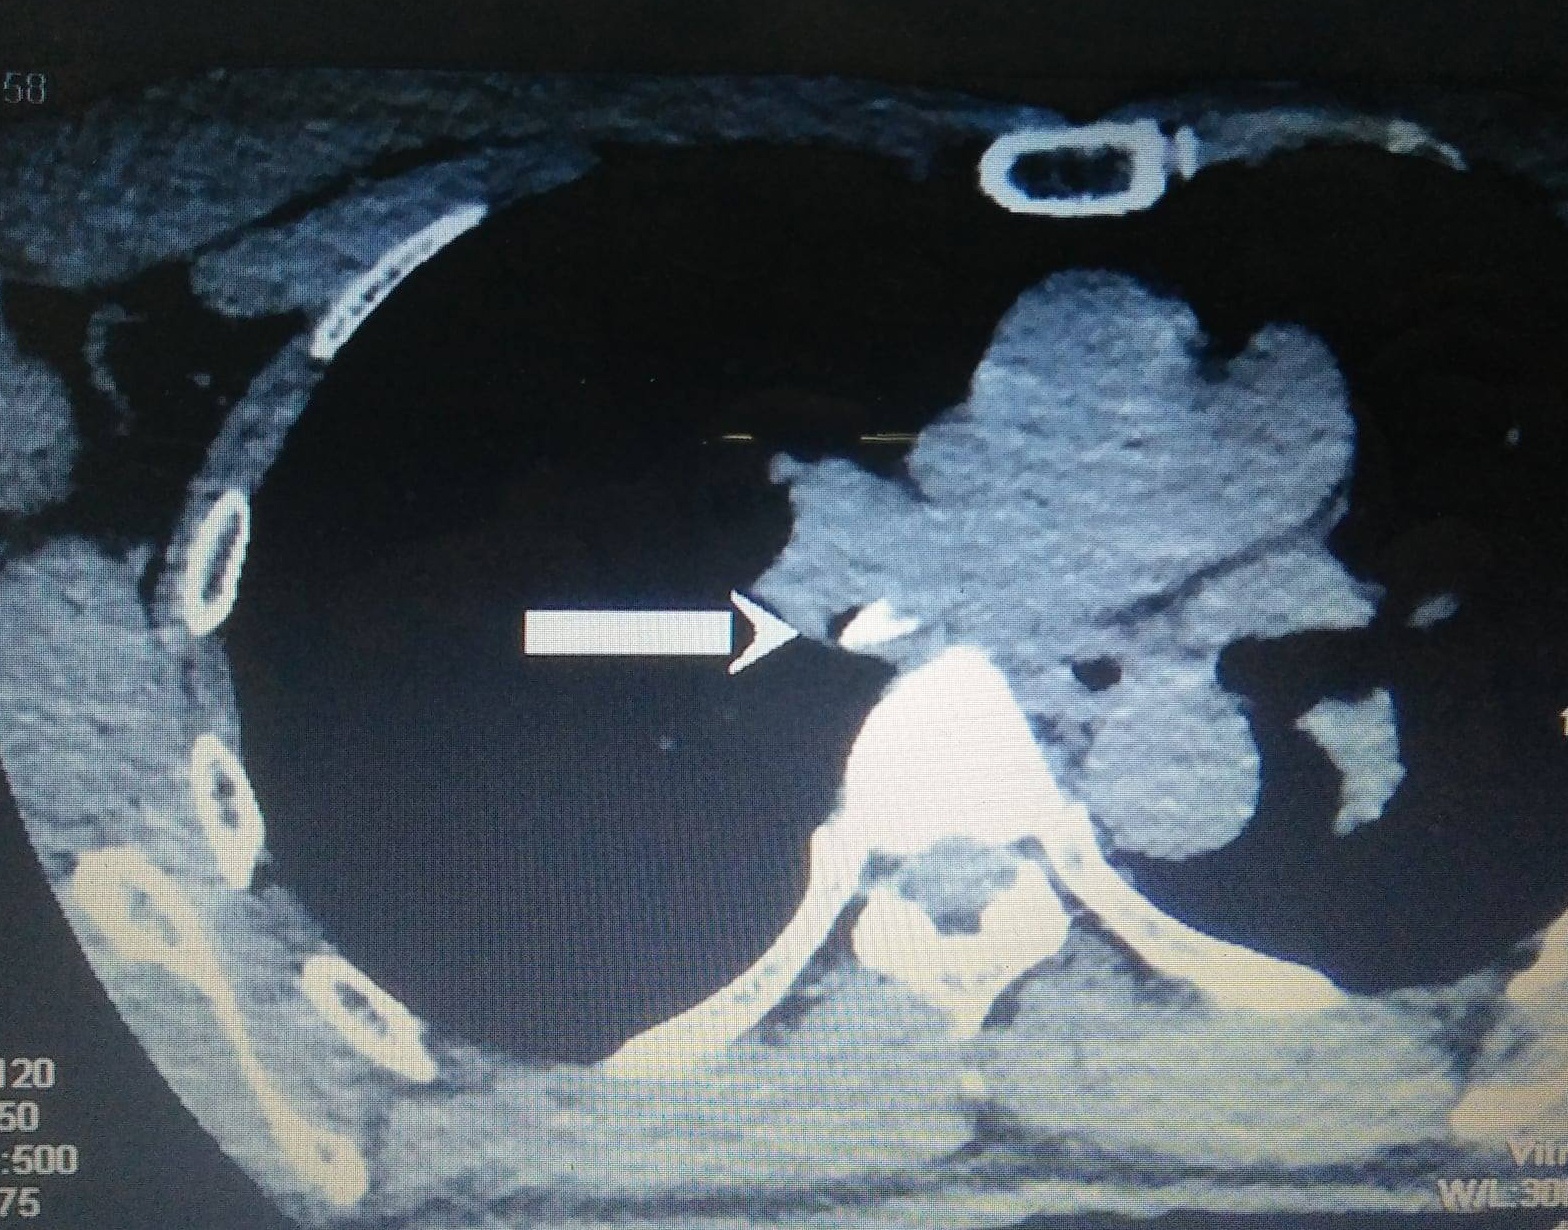

Trước đó, bệnh nhân nhập viện trong tình trạng khó thở, đau tức ngực, ho điều trị lâu ngày không khỏi. Kết quả CT cho thấy dị vật phế quản thùy dưới, ứ khí trong phổi.

| Xương cá nằm cắm chặt bít khí quản của bệnh nhân qua hình CT. Ảnh: BSCC. |

Khi về nhà, người bệnh vẫn đau, khó thở nên tìm đến Bệnh viện Tai Mũi Họng. Từ kết quả CT, bác sĩ phát hiện xương cá có kích thước 0,5x0,2 cm, bít chiếm hết phế quản. Các bác sĩ đã phẫu thuật lấy dị vật ra khỏi phổi bệnh nhân.

Xương như cây dù, cắm và bít chặt khí quản, gây phù nề viêm mạc. Bệnh nhân đã được các bác sĩ nội soi lấy được xương ra, hút mủ ra điều trị bằng kháng sinh, tránh tình trạng vỡ mạch máu, tử vong.